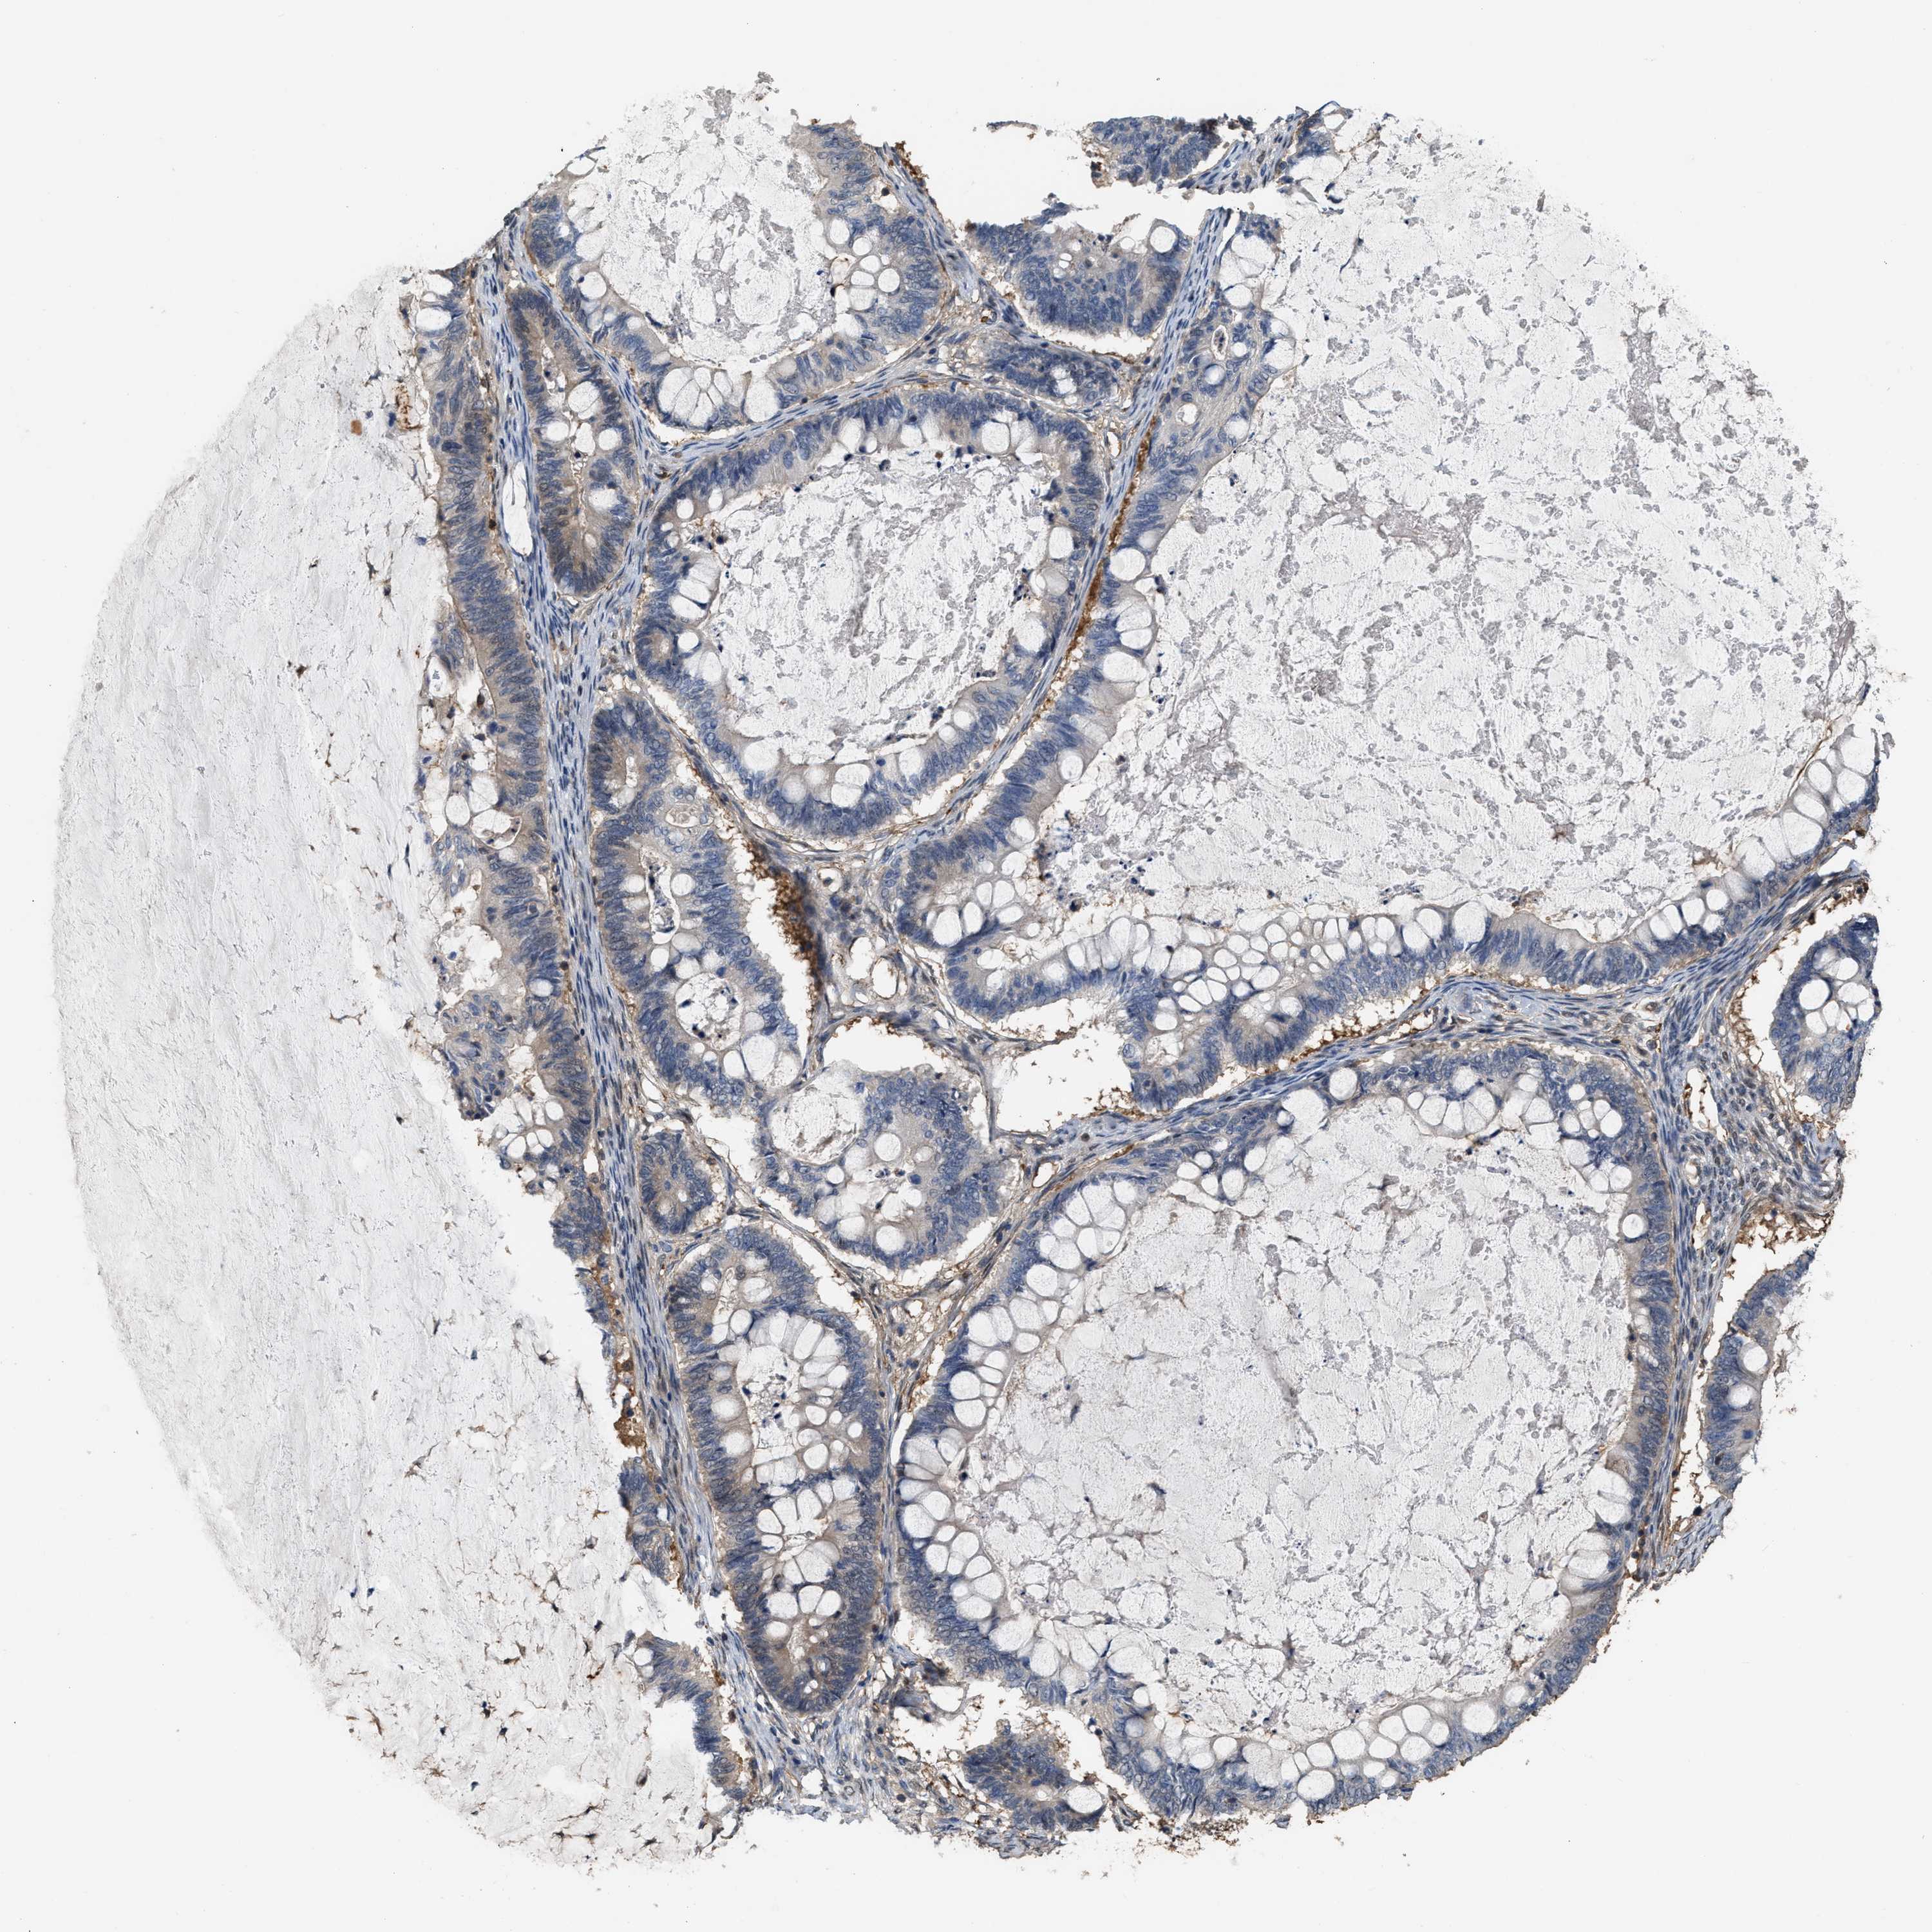

OVARIAN CANCER - Protein expressioni

A mouse-over function shows sample information and annotation data. Click on an image to view it in a full screen mode. Samples can be filtered based on level of antibody staining by selecting one or several of the following categories: high, medium, low and not detected. The assay and annotation is described here.

Note that samples used for immunohistochemistry by the Human Protein Atlas do not correspond to samples in the TCGA dataset.

Antibody stainingi

Antibody staining in the annotated cell types in the current human tissue is reported as not detected, low, medium, or high, based on conventional immunohistochemistry profiling in selected tissues. This score is based on the combination of the staining intensity and fraction of stained cells.

Each image is clickable and will lead to virtual microscopy that enables deeper exploration of all samples and also displays staining intensity scores, fraction scores and subcellular localization as well as patient and tissue information for each sample.

Antibody HPA019735

Staining

High

Medium

Low

Not detected

Intensity

Strong

Moderate

Weak

Negative

Quantity

>75%

75%-25%

<25%

None

Location

Nuclear

Cytoplasmic/membranous

Cytoplasmic/membranous,nuclear

Cystadenocarcinoma, serous, NOS

Carcinoma, endometroid

Cystadenocarcinoma, mucinous, NOS

Carcinoma, NOS